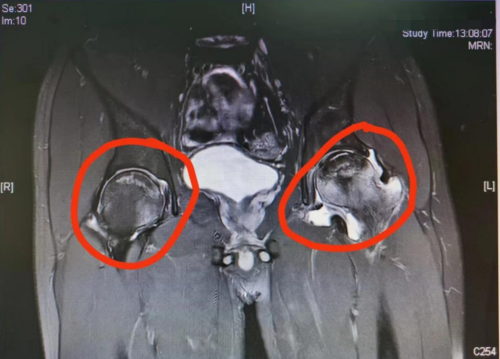

标记处为股骨头坏死磁共振下表现

23岁的叶戎(化名)近期感觉到左髋部疼痛,来到香港马会app (南华大学附属香港马会app )运动医学、关节骨病科门诊就诊,却被医生告知患上了“双侧股骨头缺血性坏死、左侧合并股骨髋臼撞击征。”追溯病因,医生分析和他6年来大量饮酒有关。

股骨头坏死又称股骨头无菌性坏死,或股骨头缺血性坏死,是骨坏死的一种。股骨头局部血运不良,引发股骨头血液循环障碍,从而使得股骨头进一步缺血、坏死、骨小梁断裂、股骨头塌陷的一种病变。